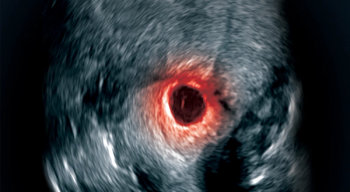

CSP is a challenge but management is possible with a multidisciplinary approach.